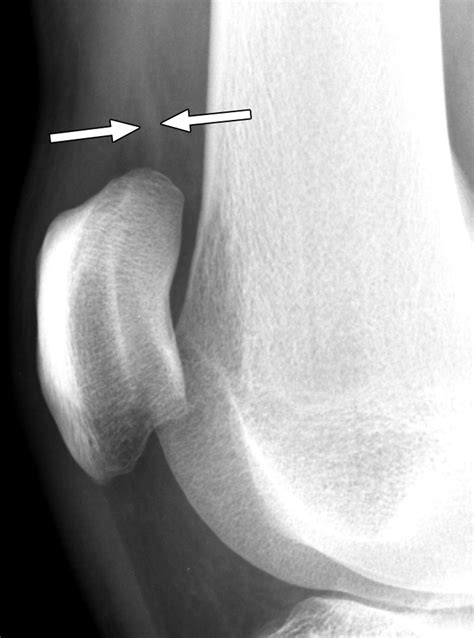

Diagnosing Joint Effusion Knee

Diagnosing joint effusion knee typically involves a combination of physical examination and diagnostic tests. The healthcare provider will:

• Ask about the patient's medical history and symptoms.

• Perform a physical examination of the knee, checking for swelling, tenderness, and range of motion.

• Order diagnostic tests, such as X-rays, MRI, or ultrasound, to visualize the joint and surrounding structures.

• Perform a joint aspiration, where a small amount of fluid is removed from the knee joint using a needle. This fluid can be analyzed to determine the cause of the effusion.